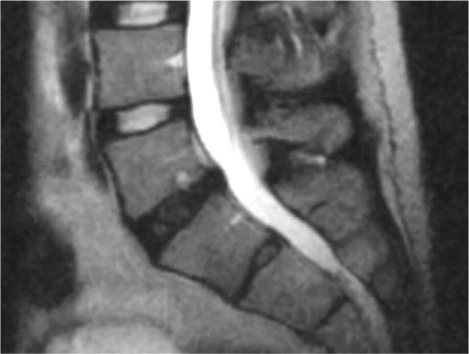

Degenerative Disc Disease (DDD)

Despite the term “disease”, DDD describes the progressive wear and tear of intervertebral discs: loss of water content, loss of disc height, and changes in disc structure.